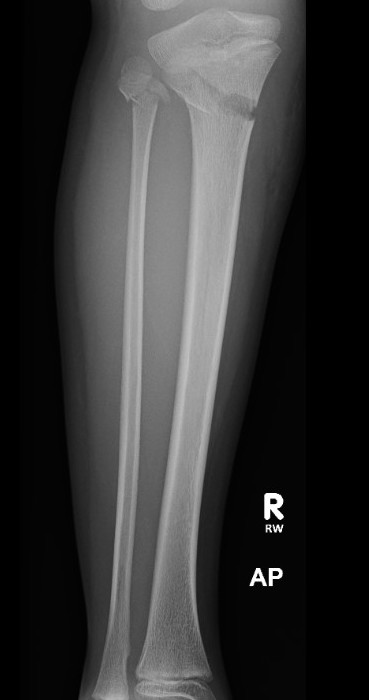

Proximal metaphyseal tibial fracture

Cozen phenomenon

Delayed valgus deformity secondary to medial tibial elongation

Valgus malalignment